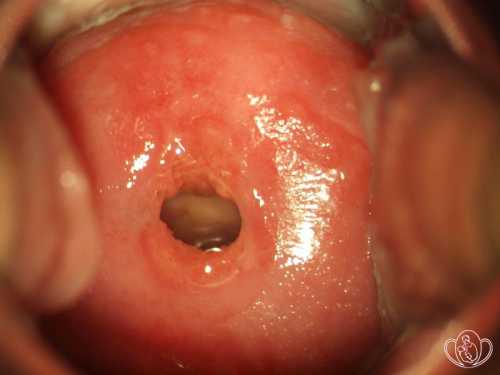

Цервицит шейки матки

Заболевание, которое не было адекватно и вовремя пролечено в острую стадию, хронизируется. Признаки хронического цервицита выражены слабее или практически отсутствуют. Выделения приобретают мутно слизистый характер, плоский эпителий влагалищной части шейки замещается цилиндриче ским из Читать далее